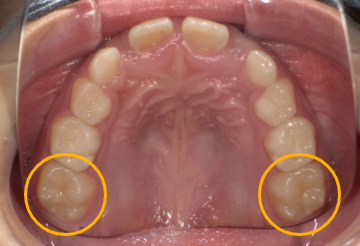

- 第一大臼歯が萌出している

- 乳犬歯と第1乳臼歯・第2乳臼歯の乳歯が残っている

第一大臼歯が萌出している

第一大臼歯は、前から6番目の永久歯のことを指します。インビザラインファーストは、第一大臼歯が1本以上生えていることが条件となっています。

乳犬歯と第1乳臼歯・第2乳臼歯の乳歯が残っている

インビザラインファーストとは、乳犬歯と第1乳臼歯・第2乳臼歯の乳歯が残っている場合に適応となります。

乳犬歯と第1乳臼歯・第2乳臼歯の乳歯は、上顎と下顎それぞれ左右対称に生えていますが、そのうち3ヶ所に乳歯が2本以上残っている必要があります。